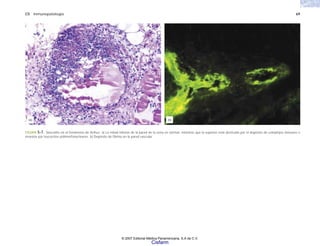

FIGURA 5-1. Miastenia gravis. a) Microfotografía de una placa neuromuscular en la que se ha teñido el autoanticuerpo (IgG) con un anticuerpo anti-IgG marcado con peroxidasa. b)

Electromicrografía de parte de una placa neuromuscular, con el anticuerpo depositado en la membrana postsináptica, que es donde se encuentran los receptores de la acetilcolina. (Tomado

de Sahashi K, y cols. Mayo Clinic Proc 52:267-280. 1977.)